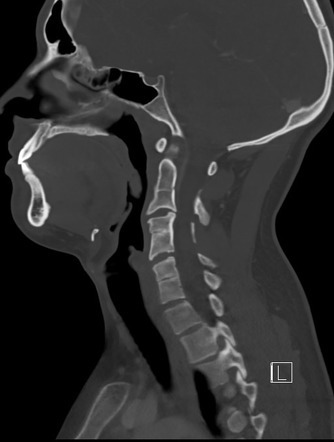

Klippel Feil syndrome

vertebral segmentation anomalies (more than two)

short neck, low hairline and restricted neck motion

A/w sprengel deformity (congenital elevation of the scapula)